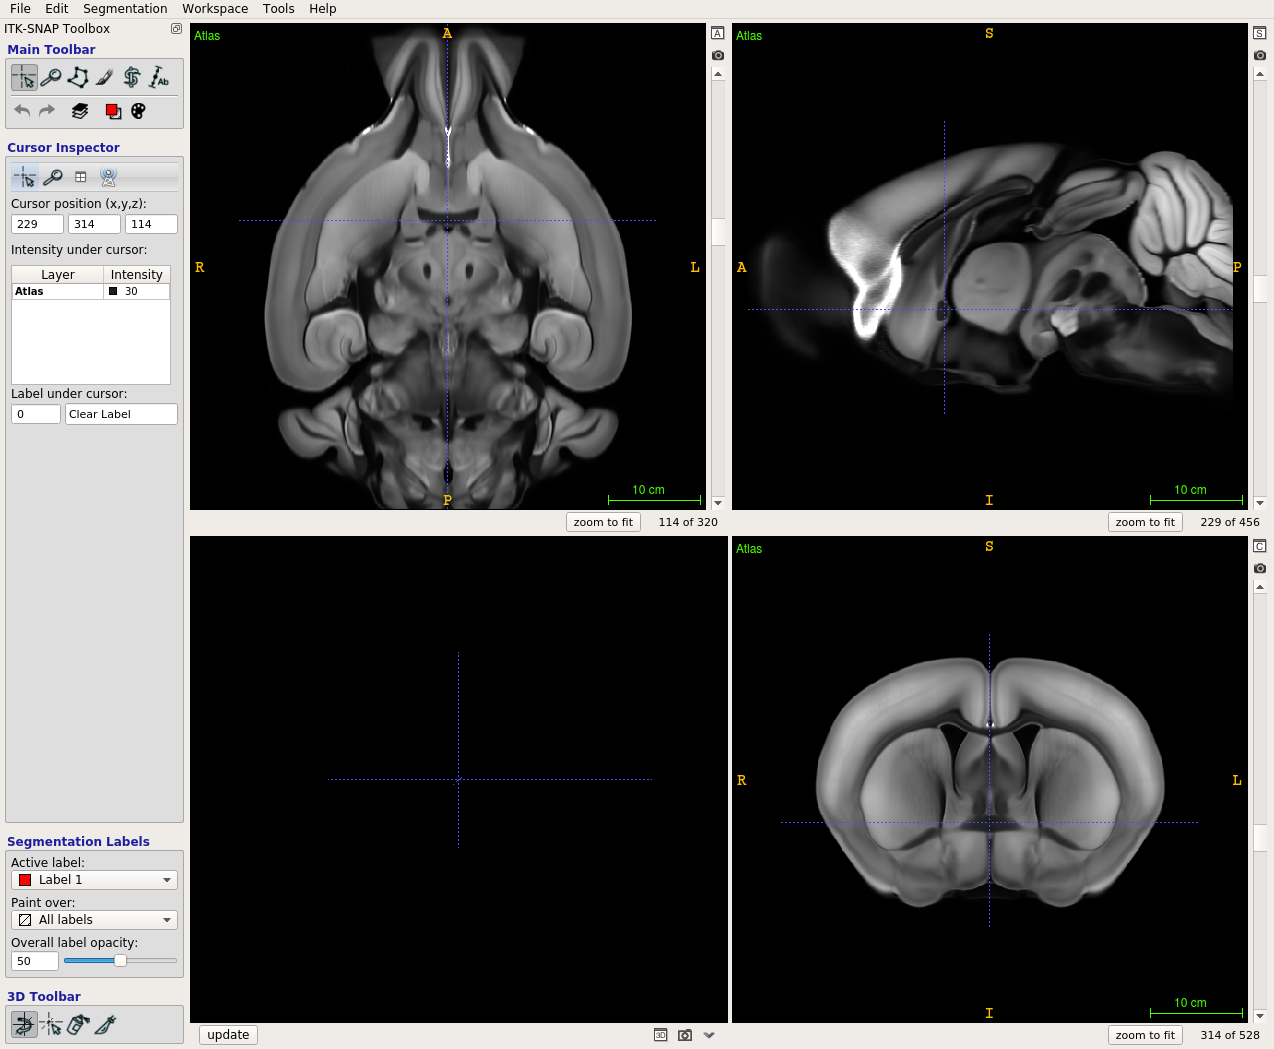

Scalable Brain Atlas  Coronal3d

Mouse - Allen Mouse Brain Common Coordinate Framework version 3

About this atlas